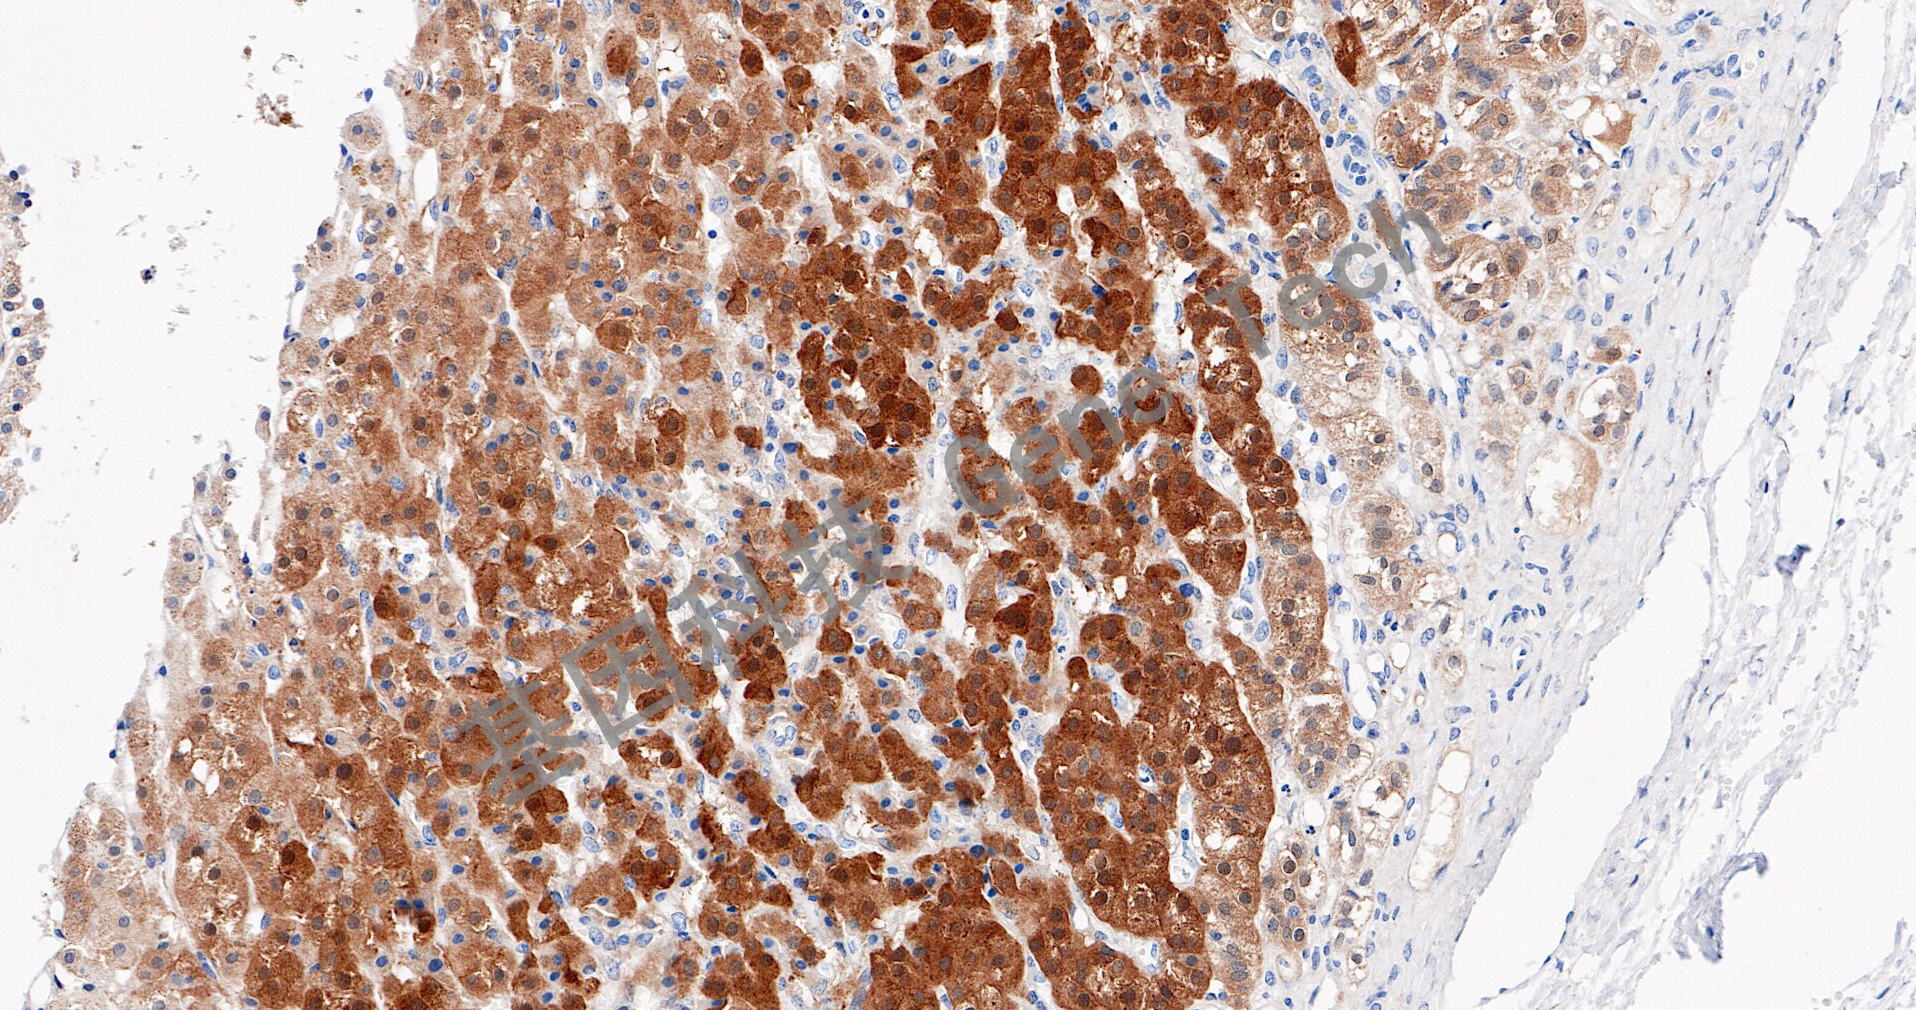

| 肾上腺皮质石蜡切片,用 CYP11B2(GT2569)染色,细胞浆阳性,DAB 显色。 | ||

| 预处理:高pH热修复 | 阳性部位:细胞浆 | 阳性对照:肾上腺皮质、肾 |